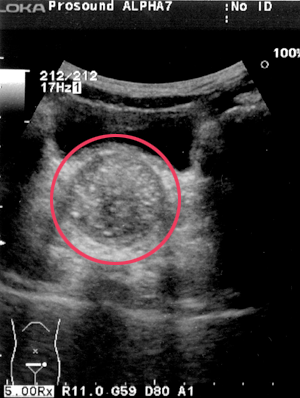

2.習慣性便秘の浣腸後の直腸

便貯留のためか、排便後も直腸径が縮小しない。